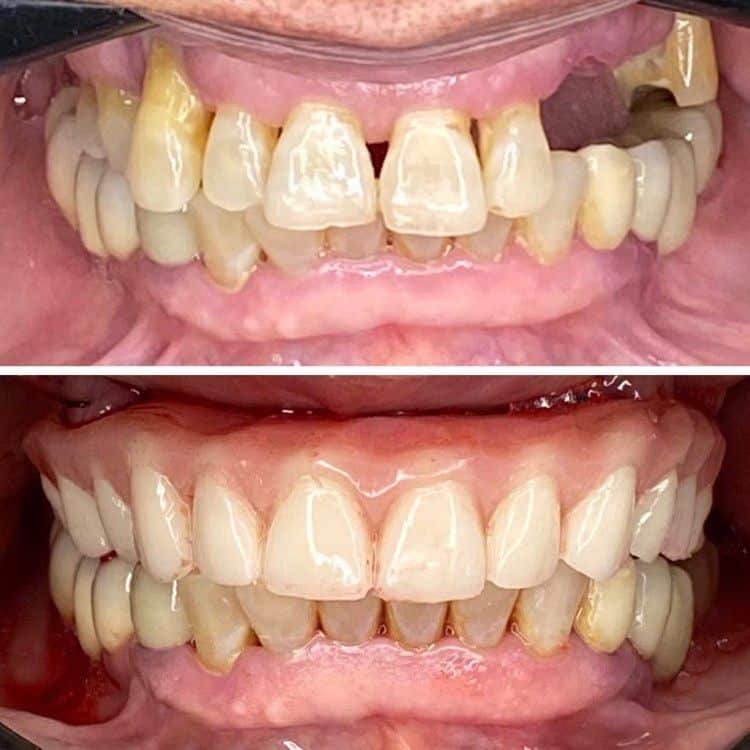

Case 005 Case: Técnica de ancoragem esquelética “All on Four STD” pelo Dr. Carlos Franza

Formado há 20 anos, o experiente Dr. Carlos Franza tem como foco de trabalho casos complexos de reabilitação total.

Atua no estado de São Paulo desde 2002 na área da implantodontia e Bucomaxilo, buscando sempre parcerias e interações de grandes profissionais da área no desenvolvimento e operacionalidade de novas técnicas buscando acima de tudo, satisfação dos pacientes.